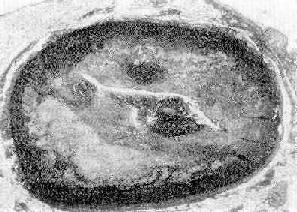

病变特点:粥样硬化斑块的分布多在近侧段,且在分支口处较重;早期,斑块分散,呈节段性分布,随着疾病的进展,相邻的斑块可互相融合。在横切面上斑块多呈新月形,管腔呈不同程度的狭窄。有时可并发血栓形成,使管腔完全阻塞(图8-28,图8-29)。根据斑块引起管腔狭窄的程度可将其分为4级:Ⅰ级,管腔狭窄在25%以下;Ⅱ级,狭窄在26%~50%;Ⅲ级,狭窄51%~75%;Ⅳ级,管腔狭窄在76%以上。

图8-28 冠状动脉粥样斑块并发血栓形成

图示左前降支粥样斑块,累及动脉壁四周,斑块底部粥样物中含大量胆固醇结晶;管腔被血栓阻塞(男性,50岁)